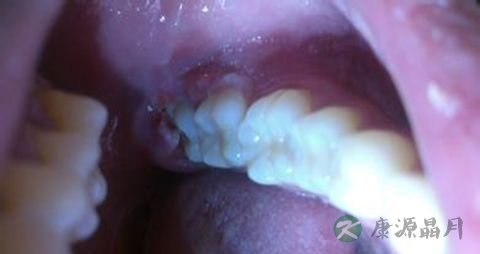

不管是什么原因的牙周炎,这部分患者在平时生活中都要特别的注意,那就是尽量的不要吃过硬的食物。可以说大家对各种各样的坚果、干果类似物都非常的喜欢,专家也指出这些食物都是非常健康的零食,过量食用也不用担心会发胖。但对于患有牙龈炎的患者而言,如果在日常生活中过量食用这类食物的话,势必会导致炎症更加严重。

比如像松子、山核桃、瓜子等,这类食物中含有的营养物质都是非常丰富以及健康的,但患有各种牙龈病的患者应该尽量少吃。